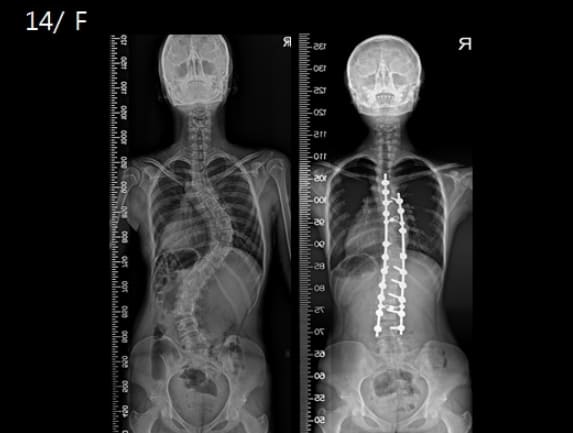

다리를 꼬고 앉으면 다리와 연결된 골반이 한쪽으로 올라가 틀어진다. 골반이 휘면 몸의 균형을 잡기 위해 척추도 함께 휜다. 꼬아 올린 다리에 실렸던 힘이 허리 쪽으로 옮겨가기 때문이다. 다리 꼬고 앉는 자세가 습관으로 굳어지면 척추가 S자로 휘는 척추측만증이 발생하게 되며 더 심해지면 척추디스크를 유발하기도 한다.

부천 연세제일병원 손준석 병원장은 “서 있을 때 양측 어깨 높이가 좌우 비대칭으로 차이가 나거나 골반의 높이가 좌우 비대칭인 경우 척추측만증을 의심해볼 수 있다”고 설명한다.

손준석 병원장은 “척추측만증은 서서 땅을 짚을 때 손바닥이 땅에 닿지 않고 한쪽 등이 튀어 올라와 있다거나 등을 바닥과 평행하도록 앞으로 구부렸을 때 한쪽 등이나 엉덩이가 한쪽으로 치우쳐 있는 모습을 관찰함으로써 진단할 수 있다”고 안내했다.